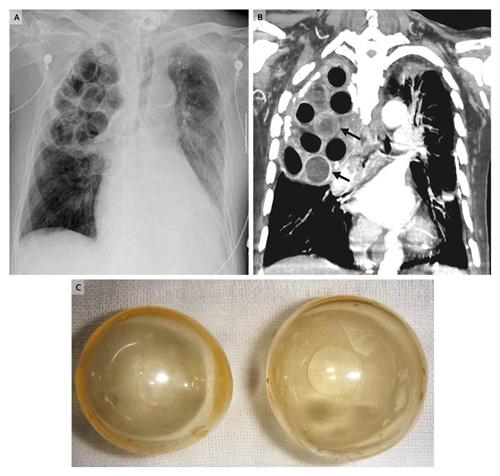

相关图片